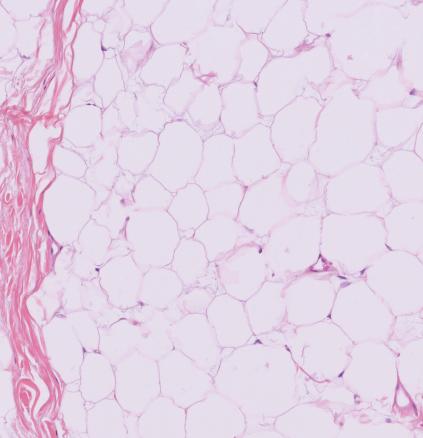

Le diagnostic est en général évoqué dès l’examen clinique, mais seule l’analyse histologique permet d’être formel, avec la mise en évidence d’une prolifération d’adipocytes matures sans cellule atypique (fig. 2).